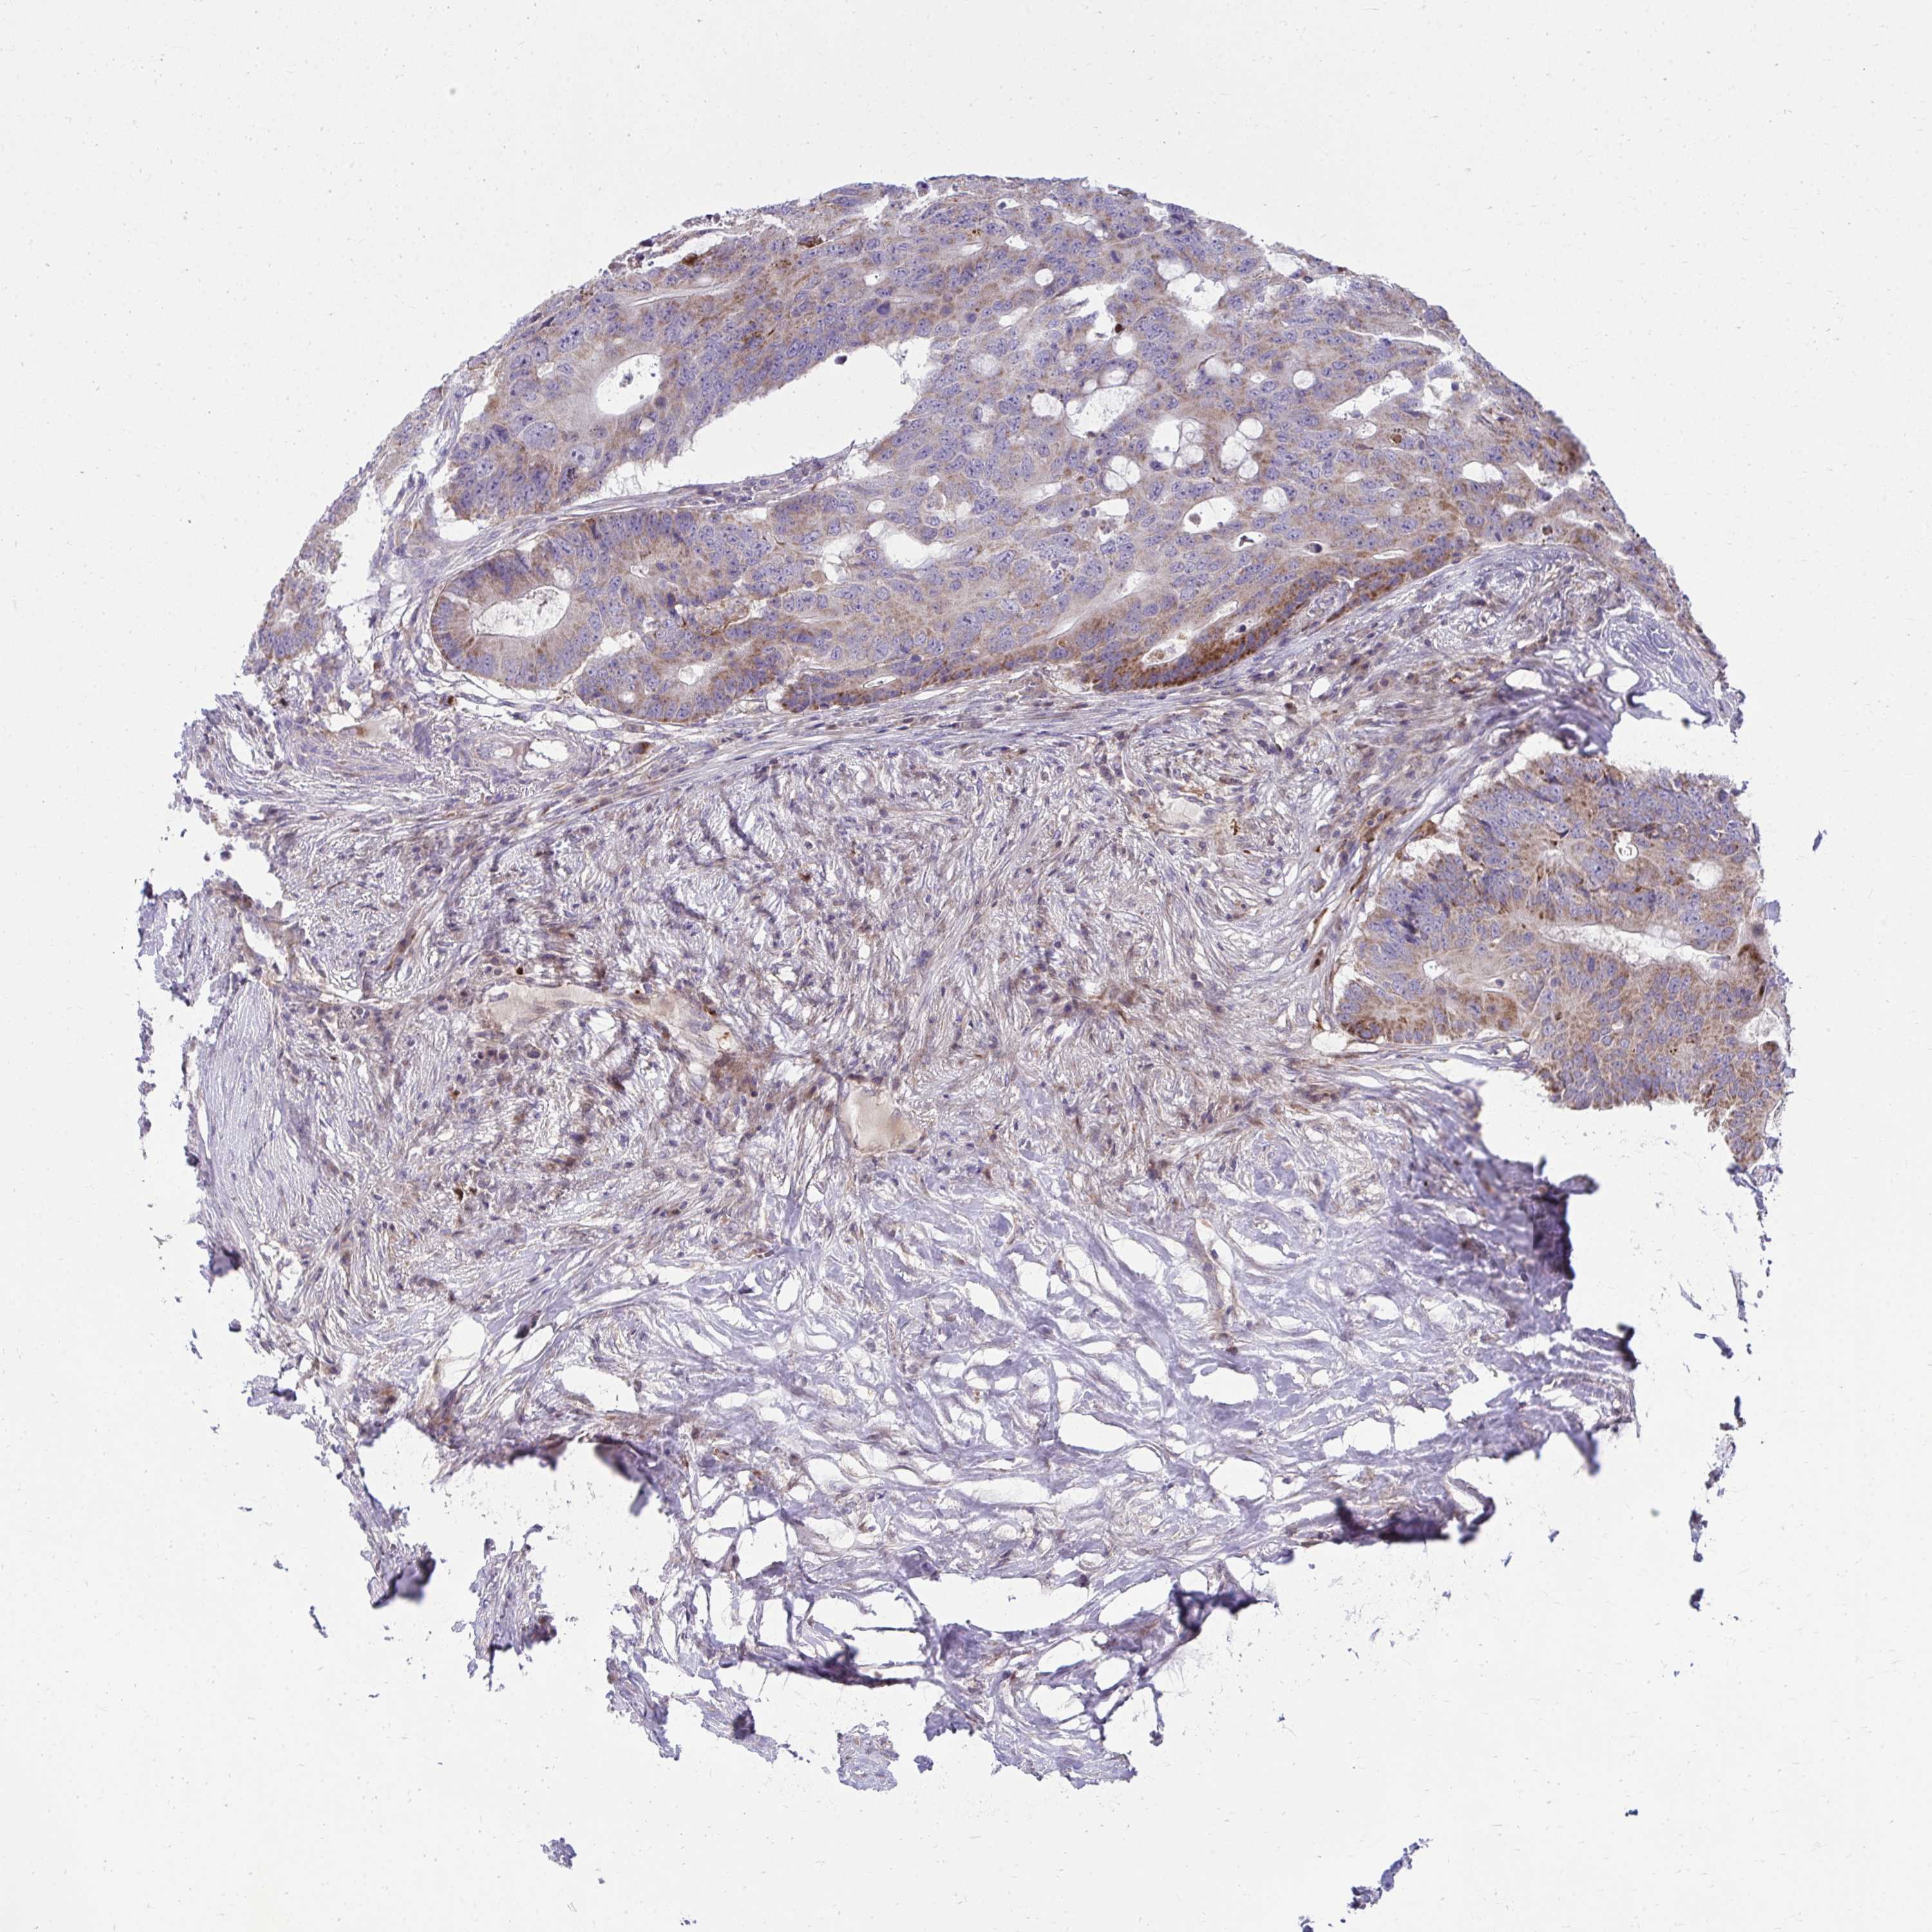

CANCER COLORECTAL CANCER Show tissue menu

Colorectal cancer

Rectum adenocarcinoma